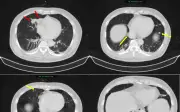

Bệnh viện Bạch Mai vừa công bố trường hợp nam bệnh nhân mắc đồng thời ung thư phổi và tuyến tiền liệt, một ca hiếm gặp. Nhờ chẩn đoán chính xác và phác đồ điều trị phù hợp, bệnh nhân đã có đáp ứng tích cực sau 2-3 tháng.

Một người đàn ông 63 tuổi tại Bệnh viện Bạch Mai được chẩn đoán mắc đồng thời ung thư phổi và ung thư tuyến tiền liệt chỉ trong chưa đầy 2 tháng, từ dấu hiệu tiểu khó ban đầu. Ca bệnh hiếm gặp này nhấn mạnh tầm quan trọng của chẩn đoán chính xác và điều t